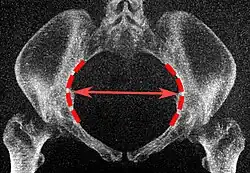

Tomografias computadorizadas de baixa dose em 3D podem ser usadas para estimar os principais parâmetros da pelvimetria:[4]

| Parâmetro | Projeção de intensidade máximas[5] | Cortes finos | Pontos finais | Medidas normais | |

|---|---|---|---|---|---|

| Abertura superior da pelve | Diâmetro transverso da abertura superior |

|

Plano coronal |

As linhas iliopectíneas, na maior distância transversa. | 13 a 14,5 cm.[4] |